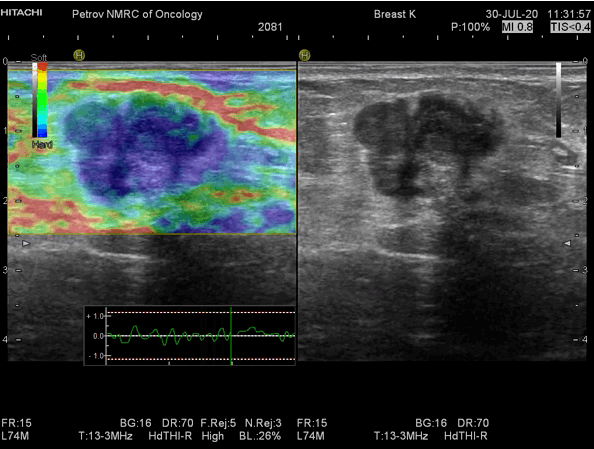

Термография — это метод визуализации тепловых изображений тела человека, основанный на регистрировании температуры кожи. Каждая аномалия в ткани, в т.ч. и злокачественные образования, вызывает изменения в кровообращении и метаболизме, что проявляется в изменении температуры. Используя специальное оборудование, специалисты получают тепловой снимок, на котором выделяются области с повышенной или пониженной температурой.

В случае с раком молочной железы, опухоль, как правило, сопровождается усилением кровоснабжения и метаболизма, что приводит к локальному повышению температуры области. Термография позволяет выявить эти изменения еще до появления заметных симптомов или рентгенологических признаков, что делает её ценным инструментом для ранней диагностики.

- Съемка тепловых изображений: с помощью термографа снимается тепловое изображение каждой груди.

- Обработка и интерпретация данных: специальное программное обеспечение анализирует полученные снимки, выявляя участки с аномальной тепловой активностью.